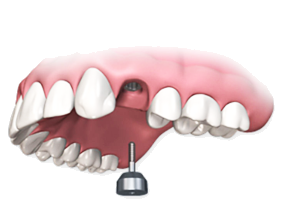

Установка и приживление имплантата

Хирург вживляет в кость имплантат из титана.

Операция занимает около 20 минут. Вместе с подготовкой, анестезией и наложением швов около 1 часа. Интеграция имплантата занимает от 2-х до 6-ти месяцев.

Устанавливается формирователь десны

Через несколько месяцев, после приживления имплантата,

на него устанавливается титановый колпачек. Он готовит десну к появлению в этом месте нового зуба.

Спустя 2 недели снимаем слепки

Снимаем слепки и передаем в собственную зуботехническую лабораторию для 3D проектирования и производства коронок.

Установка коронки

Откручиваем формирователь десны и устанавливаем индивидуально спроектированный абатмент и коронку. В результате зуб неотличим от настоящего и имеет надежный корень в виде срощенного с костью титанового имплантата.